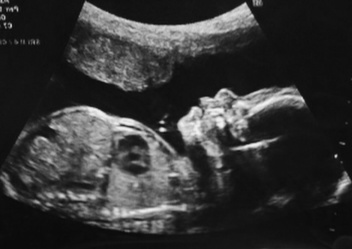

Муж поддерживает, говорит, что Ди непременно откормит щечки, что на следующем УЗИ (назначили в динамике каждые две недели+допплер) она снова начнет обгонять сверстников по всем параметрам. Как же я хочу, чтобы так и было! А вот и она, крохотная и беззащитная, наша Динь. Смотрю на нее, понимаю, как плохо ей сделала и слезы наворачиваются: как я могла? Я не переживу, если что-то случится!=(

Копалась в телефоне и нашла ЕГО: наше первое УЗИ, 6 недель.

И самое "свежее": 17 недель.

Как же она выросла, наша Совушка! Сижу реву от умиления=)